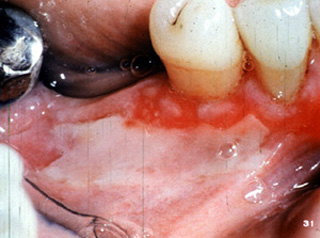

El penfigoide benigno tiene una marcada tendencia a involucrar la encía marginal. La descripción clínica a menudo usada para estas lesiones es "gingivitis descamativa" Debe señalarse que ésta es sólo una descripción clínica y no un diagnóstico definitivo. En la encía  tiene una marcada apariencia eritematosa.

Aquí hay otro paciente con la encía afectada por la enfermedada..